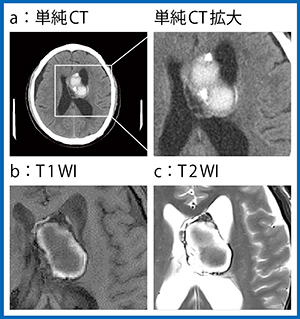

症例1(58歳,男性)は,既往なし,初期症状として頭痛と複視を発症した。近医での頭部CTで出血を伴う脳腫瘍が認められ,当院にて造影CT,造影MRI,脳血管撮影を行い,開頭腫瘍摘出術が行われた。

単純CTでは腫瘍の大部分は淡い高信号で,辺縁の一部に塊状の強い高信号が認められたが(図1 a),同部位はT1強調画像(T1WI)(b),T2強調画像(T2WI)(c)でも出血/石灰化の区別が困難だった。また,T2*強調画像(T2*WI)でも,時期の異なる出血があることは指摘できるものの,石灰化の有無は判断できなかった(図2 a)。これに対してQSMでは,腫瘍の中央は高信号に描出されるため出血が,辺縁は非常に低信号であることから磁化率の低い石灰化が示唆された(図2 b)。また,CT(図1 a)で強い高信号を示した部分は,QSM(図2 b)で低信号に描出されたことから石灰化と考えられた。MRIでは出血と石灰化の鑑別はQSMでしかできないため,質的診断にQSMは非常に役立った。

図1 症例1の単純CTと単純MRI